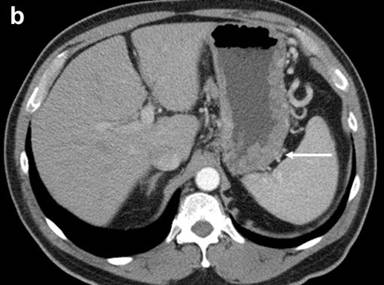

The patient was referred to our institution for consultation where he underwent repeat multiplanar MDCT with the use of 100 mL intravenous (iopromide; Ultravist® 300, Bayer, NJ, USA) contrast material delivered at 3 mL/s and imaged with a 70 s delay. Nine hundred mL oral (water) contrast was also utilized. Images were obtained at 120 kVp and 200 mAs and reconstructed at 5 mm. The pancreas was universally enlarged with a distinct rim of hypoattenuation (Figure 1). The wall of the gastric body and fundus, predominantly posteriorly, was diffusely thickened, measuring up to 1.4 cm, and had a nodular appearance (Figure 1). The gastric wall thickening spared the antrum. No hyperenhancement of the gastric wall was noted. There were additionally noted several hypodense lesions in both kidneys that were surrounded by hypovascular soft tissue (Figure 1) as well as focal jejunal wall thickening without hyperenhancement (Figure 1).

Figure 1. a. Axial MDCT image of the abdomen with intravenous and oral contrast demonstrates a thickened, “sausage-like” pancreas with a hypodense rim of tissue (arrow). b. Axial MDCT image of the abdomen with intravenous and oral contrast demonstrates a thickened and nodular appearance of the stomach wall at the level of the gastric body measuring up to 1.4 cm (arrow). c. Sagittally reformatted MDCT image of the abdomen shows the thickened and nodular gastric body wall, most pronounced posteriorly (arrow). d. Axial MDCT image demonstrates bilateral renal lesions (arrows) with a soft tissue attenuation within and immediately adjacent to the left kidney (dotted arrow). e. Axial MDCT image demonstrates focal jejunal wall thickening. |